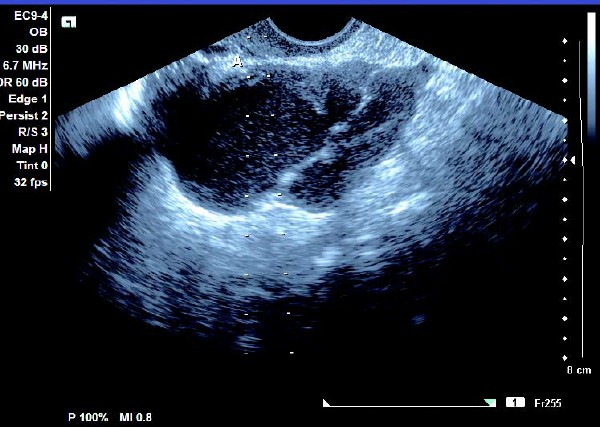

(1)单侧或双侧卵巢内显现椭圆形或圆形无回声暗区,其内充满弱回声光点,囊肿直径一般为5~6 cm,大于10 cm 的较少见。

(2)壁较厚,囊内充满细小均匀点状回声,后方回声增强。

(3)常与周围组织有粘连,边界清晰。

患者,女,35岁。每次月经量少,痛经,近来行经期延长、疼痛加重来院诊治。超声报告显示子宫前倾位,子宫体大小为:5.9cm×5.1cm×4.8cm,形态规则,边界清晰,宫避回声匀称,宫腔线居中,内膜厚度0.6cm,宫内未见异常回声。右侧卵巢内可见大小约5.2 cm×4.9cm的无回声区暗区,壁厚,内壁欠光滑,内见密集细光点,边界清晰。CDFI探测囊壁及囊腔内无血流信号。

超声提示:右侧卵巢巧克力囊肿